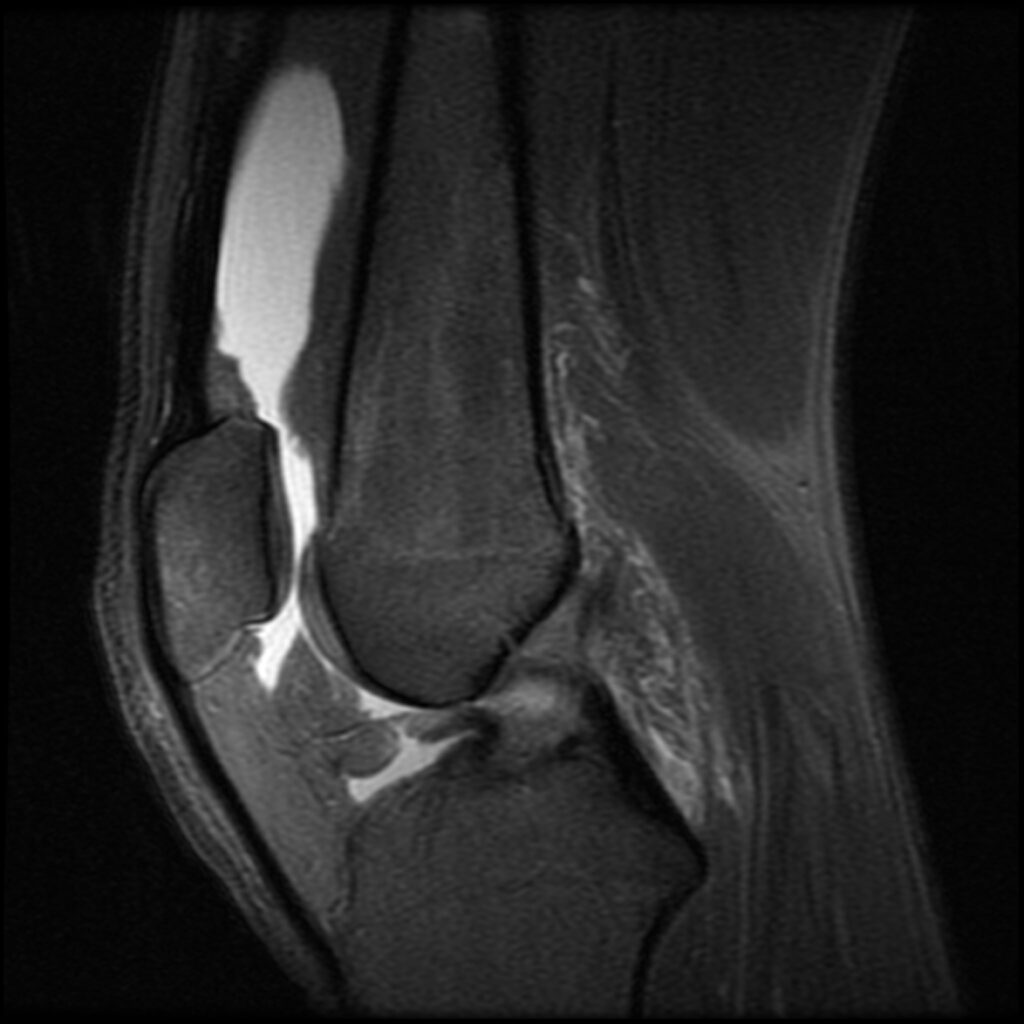

Patient P, age 20, was playing soccer when his running foot got planted and stayed in the same position while his body continued going forward and rotated around the knee. This is the pathognomonic soccer ACL injury players try to avoid when they “tuck & roll” rather than resist going horizontal. Soccer players tend to have longer careers than their American football counterparts because they never resist falling and going down. Tucking & rolling redirects the force rather than meeting the momentum head-on. The tucking part forces your bones and joints into optimal alignment and flexion, adding obstacles to injury if I may be so bold. P was given the same initial treatment and aftercare as patient D, aspirating any effusion and again treating the posterolateral origin of the ACL. His first follow-up was at 16 weeks. His MR demonstrated complete re-ligamentization of the ACL. He stated that he had already been symptom-free and back to playing soccer regularly, only wearing a neoprene sleeve to remind him to be careful.

Patient P Before

Patient P After